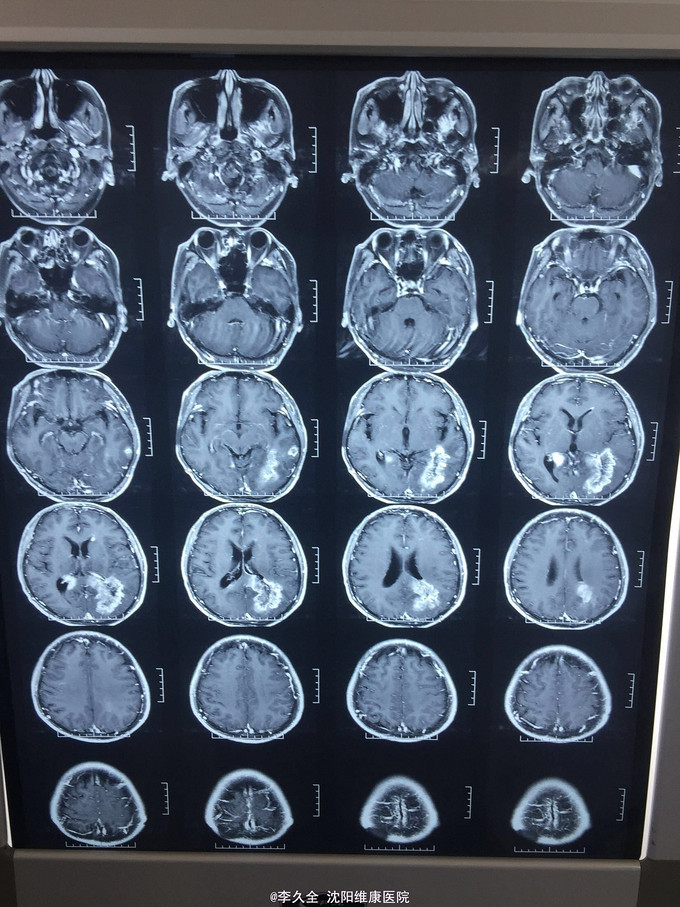

男,62岁,以头晕、视野缺损、记忆力减退、失写、失算7个月入院! 现病史:去年7月出现头晕,就诊于医院,行头CT:代诉未见异常,口服药物无效,后出现右侧视野缺损,走路撞墙、撞门,就诊于当地医院、北京协和医院,考虑“㬵质瘤”,近3个月出现近事遗忘为主,平时写字不会,计算力下降,不认识人! 既往史:2型糖尿病5年!

查体:BP:150/80mmHg,心肺腹无异常。神清,不能言语,失写、失算、失认,双曈孔等大正圆,直径3.0mm,光敏,四肢能够活动,右侧肌张力增高,巴氏征R+L-,颈强3横指,克氏征阳性! 影像MR:

1.颅内占位,胶母可能大! 2.2型糖尿病